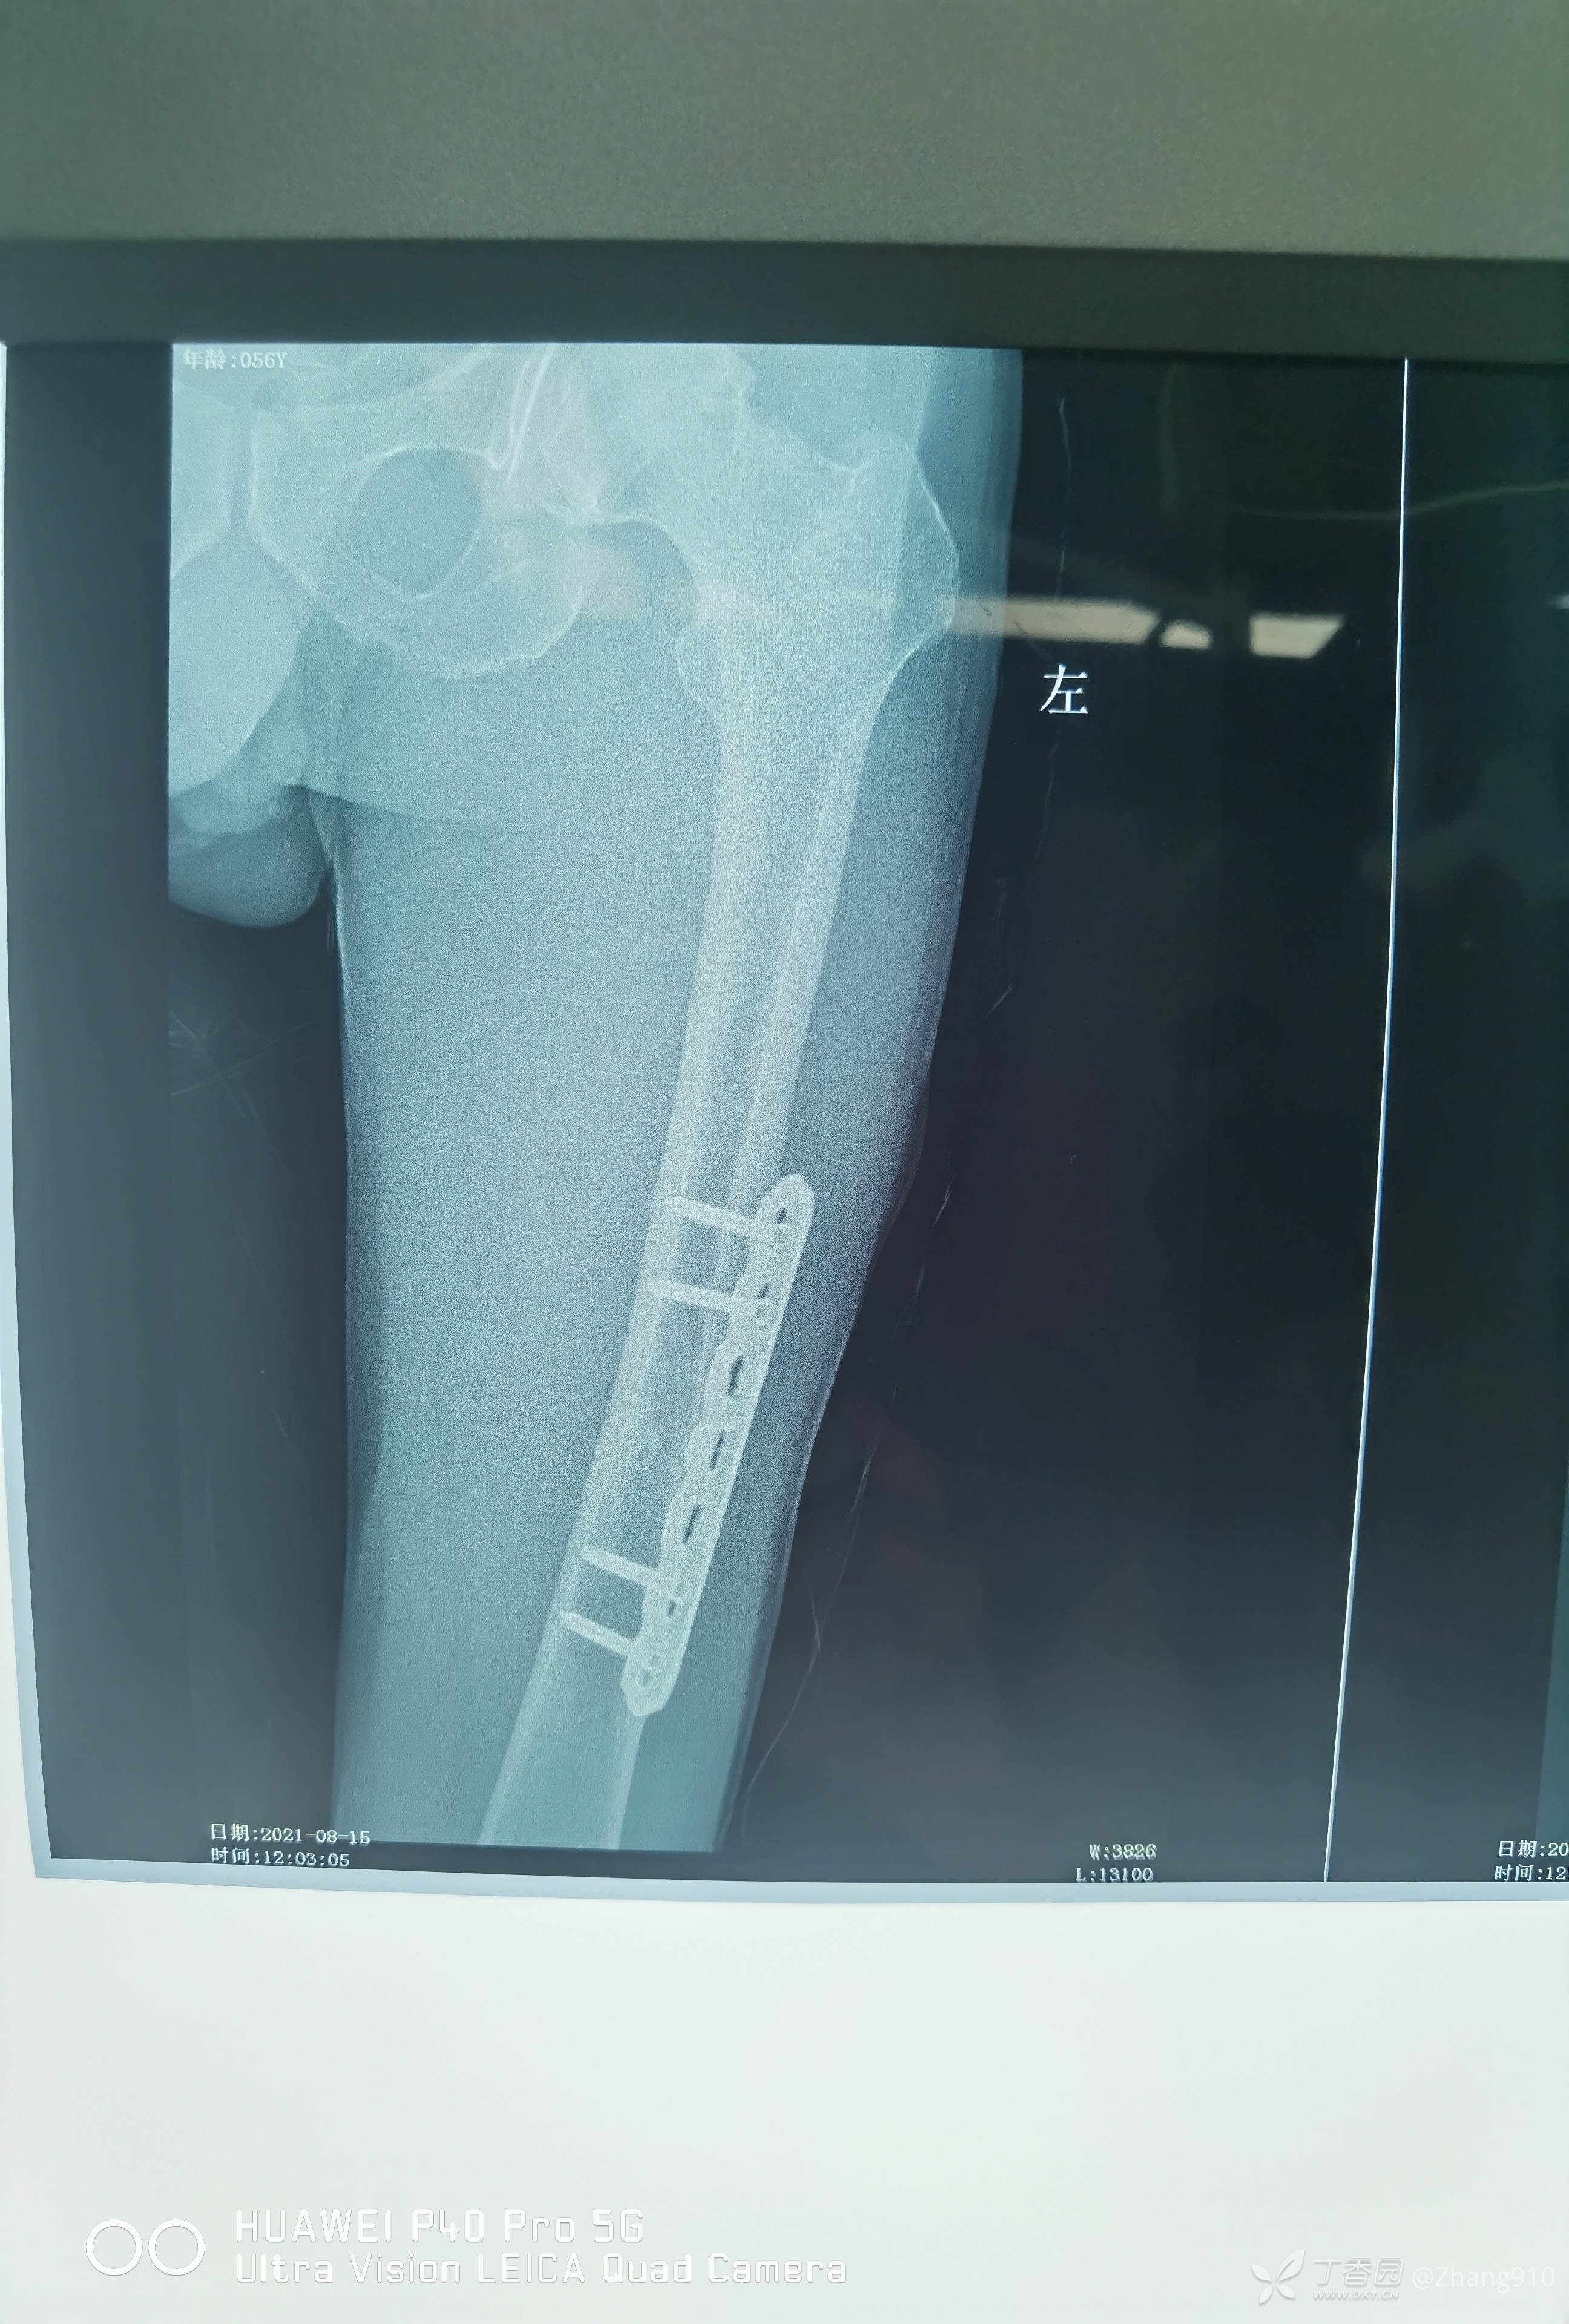

2021.08.15门诊来院,如下图:骨折愈合良好。查体未发现明显异常,各关节活动良好。

患者要求取出钢板,遂今日取出内固定。

术前X线: